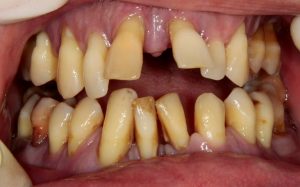

Это изначальная ситуация, та клиническая картина и те проблемы, с которыми вы приходите к доктору. И она может быть самой разнообразной, от полной катастрофы до вполне приемлемого состояния полости рта, когда требуется лишь профессиональная гигиена.

Как правило, проблемы с зубами не появляются мгновенно, а развиваются и накапливаются годами. До определенного момента, вы и ваш организм с ними справляется, а потом… приходит время обратиться к врачу.

В качестве примера возьмём двух пациентов с одинаковой клинической ситуацией — полным отсутствием зубов на одной из челюстей.

Вроде бы, одинаковая клиническая ситуация, но….

- второй пациент — это 45-летний мужчина, оставшийся без зубов из-за быстро прогрессирующего пародонтита. Вроде как, еще вчера у него были зубы, а сегодня бах! — и нет зубов. Это обстоятельство поломало ему жизнь и загнало в депрессию, испортило личную жизнь и т. д.: «Меня девчонки не любят! Кому охота встречаться с беззубым мужиком?» И вот, он обращается к стоматологу с просьбой: «Верните зубы! Такие, чтоб как настоящие!»

Займёмся вторым пациентом, 45-летним мужчиной. Напомню, что он остался без зубов в самый неподходящий момент времени, когда, если можно так выразиться, у всех мужиков только жизнь начинается.